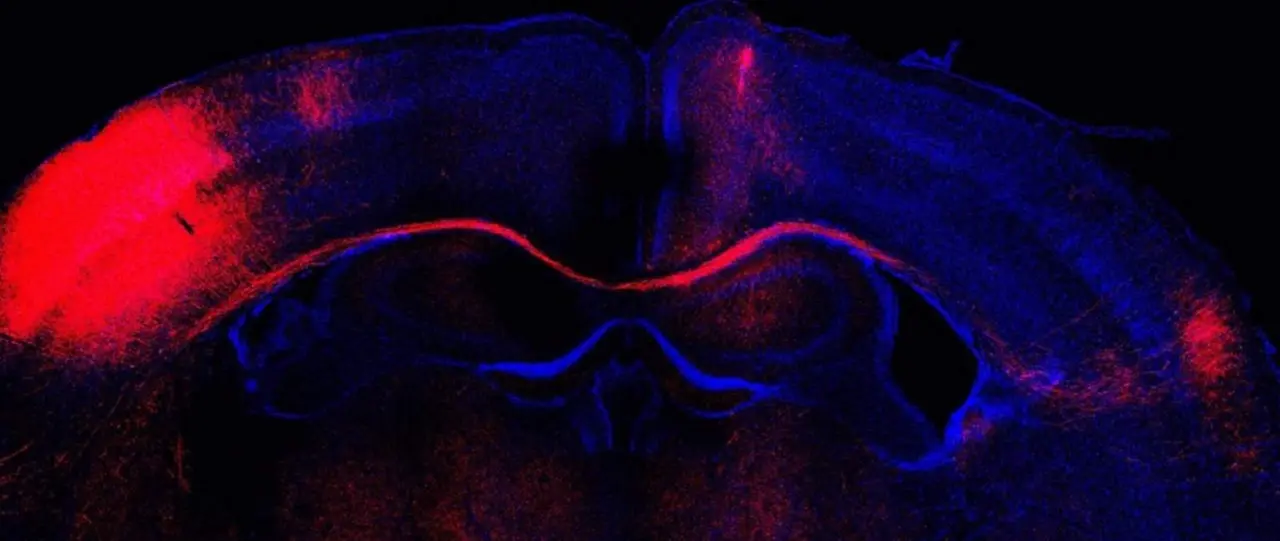

Imagen de microscopía de un corte cerebral con las conexiones formadas por neuronas (rojo). - LORENA BRAGG-GONZALO, CNB-CSIC

Un hallazgo del Consejo Superior de Investigaciones Científicas (CSIC) ha identificado cómo las neuronas inhibitorias determinan la estabilización o eliminación de las estructuras de comunicación excitatoria al filtrar las señales que reciben las neuronas excitatorias durante su maduración y, por tanto, determinan la estructura final del cerebro adulto.

"Nuestros datos demuestran que manipulaciones tempranas en las neuronas inhibitorias inducen cambios estructurales en sus vecinas excitatorias. Estas alteraciones ocasionan, en consecuencia, cambios persistentes en su manera de conectarse que afectan a un correcto procesamiento y computación de la información sensorial. La inhibición temprana en el cerebro en formación, por tanto, determina la estructura del cerebro adulto", ha señalado una de las primeras autoras del trabajo, Lorena Bragg-Gonzalo.